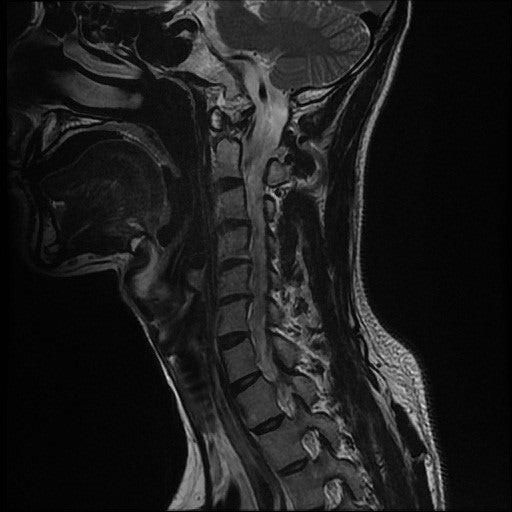

경추MRI사진과 결과지입니다.

결과지에는 디스크라고만 나와있는데

인대골화증이나 척수증은 아닌지 다시 한번 봐주시면 감사하겠습니다.

• 2번 째 사진

사진상으로 보았을때 목 디스크 주변에 염증이 있는 것으로 보이고, 추간판 탈출의 증상이 있는것으로 보입니다. 정확한 상태는 담당 주치의 선생님과 상담 받아 보시면 좋을 것 같습니다.

해당 영상의학적 검진 상 디스크에 대한 진단이 정확해보입니다. 골화증이 될려면 하얗게 생긴 띠 등이 보여야 하지만 그런 증상들이 보이지 않습니다.

일반적으로 디스크 탈출증이나 퇴해성 변화에 관련된 문제 일 수 있습니다.  MRI소견에서 인대 골화증이 의심되는 소견(인대 두께 증가)나 척추 압박이 있는 경우 그에 대한 언급이 있어야 합니다. 결과지를 의사와 상담을 통해 구체적인 진단을 받는 것이 좋습니다!

목 디스크 주변에 발생한 염증이 있는 것으로 보이는데요, 추간판 탈출의 증상이 있으신 것으로 보여집니다. 조금 더 정확한 소견은 전문의와 상담을 해보시는 것이 좋겠습니다.

위의 영상촬영본을 봤을때는 목 디스크 주변에 염증이 있는것으로 보입니다 보통 추간판탈출증(목디스크) 증상이 있습니다 담당의사랑 충분히 상담받으시고 치료계획을 세워보시는것을 권해드리고 다른병원 2군데 정도 더 가보셔서 다른의사의 의견도 들어보는것도 괜찮습니다